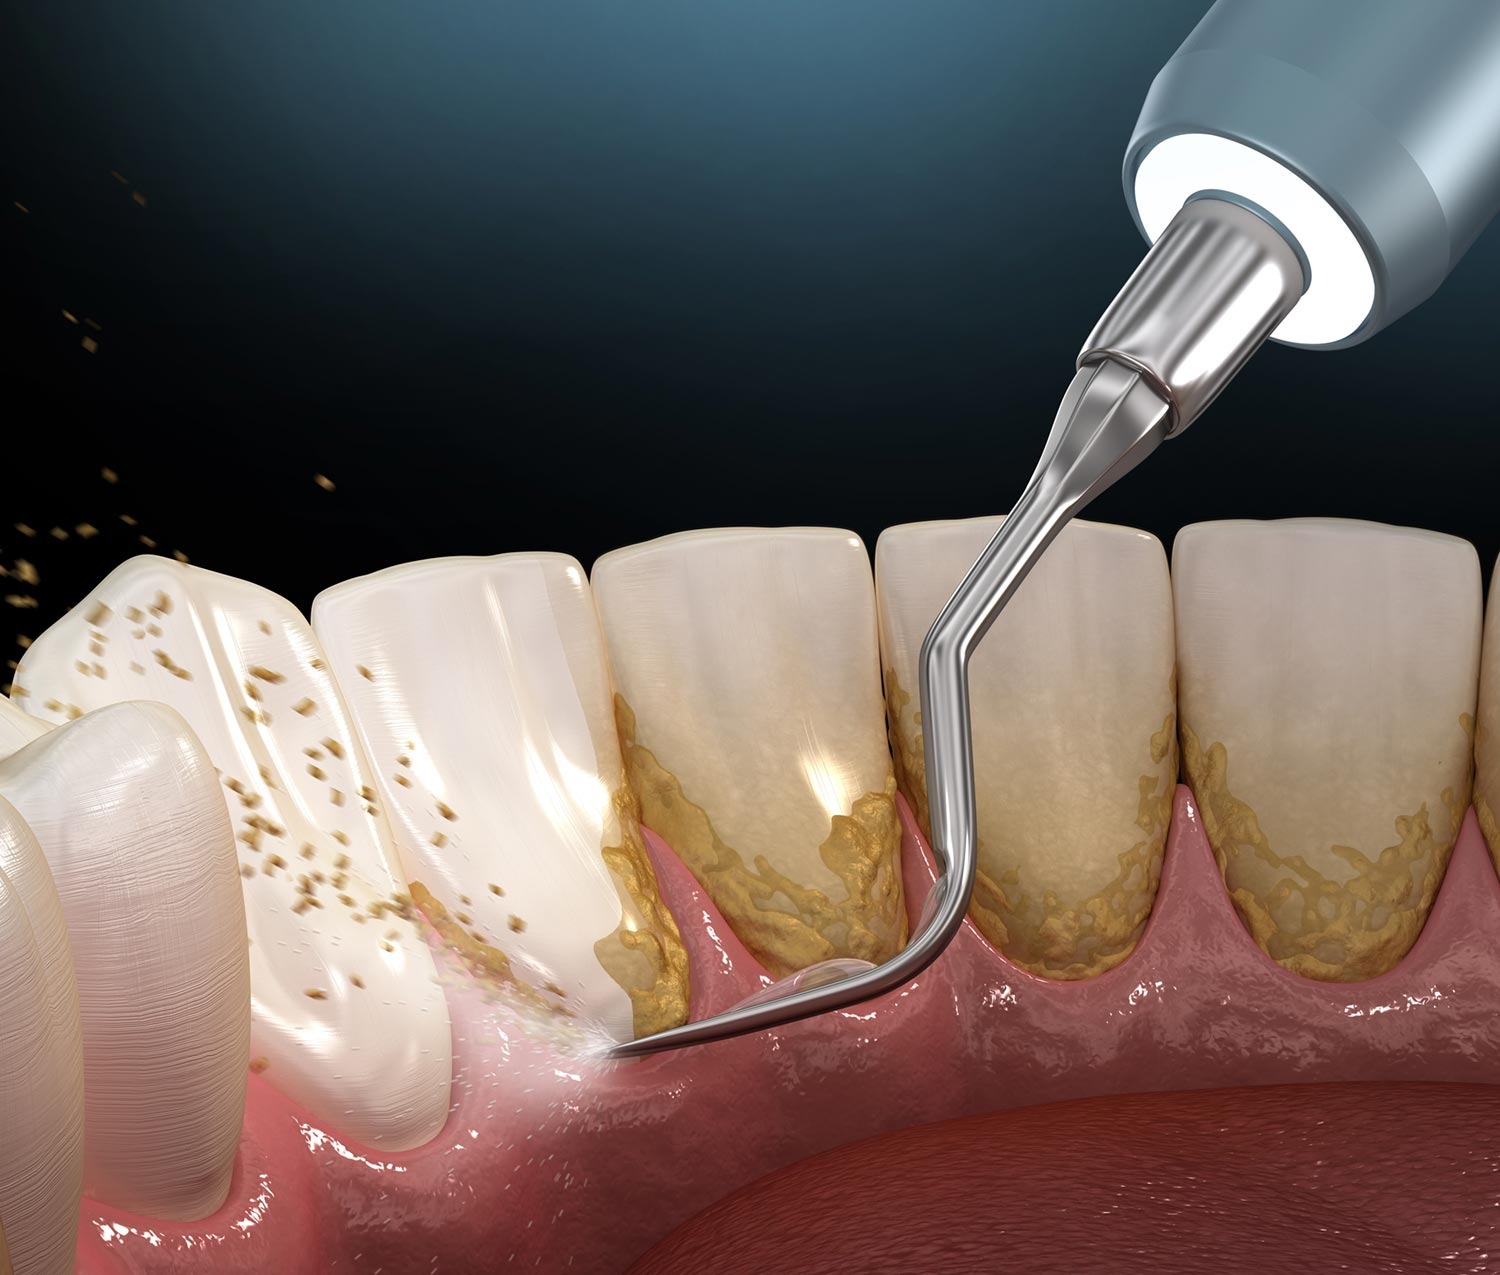

2. Deep Cleaning (Scaling & Root Planing)

The tooth roots are cleaned to remove plaque and tartar.